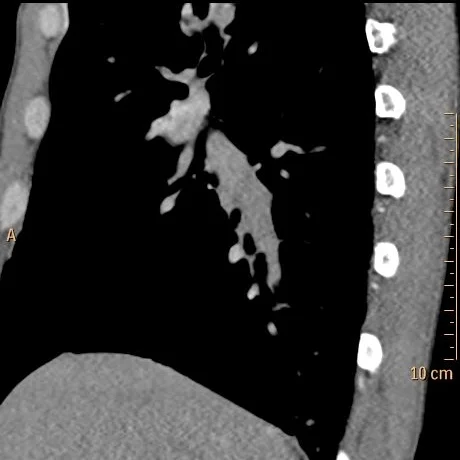

CT chest PE protocol confirms pulmonary embolism in right lower lobe